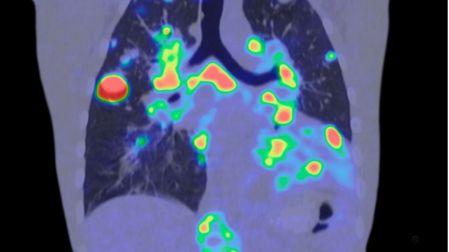

Para entender la gravedad de esta alerta, es necesario comprender qué es el pembrolizumab. Según el Instituto Nacional del Cáncer (NCI), Keytruda es un anticuerpo monoclonal que actúa como inmunoterapia. Su función es "desbloquear" el sistema inmunitario del paciente para que este pueda reconocer y atacar las células cancerosas.

- Cáncer de pulmón de células no pequeñas.

- Carcinoma de vejiga (urotelial).

- Melanoma y cáncer de mama triple negativo.

Cuando se utiliza un ejemplar falsificado, el "bloqueo" inmunológico persiste, permitiendo que el tumor avance sin resistencia. La eficacia de la inmunoterapia depende de la pureza molecular y de una cadena de frío estricta, elementos que desaparecen por completo en un producto de procedencia ilícita.